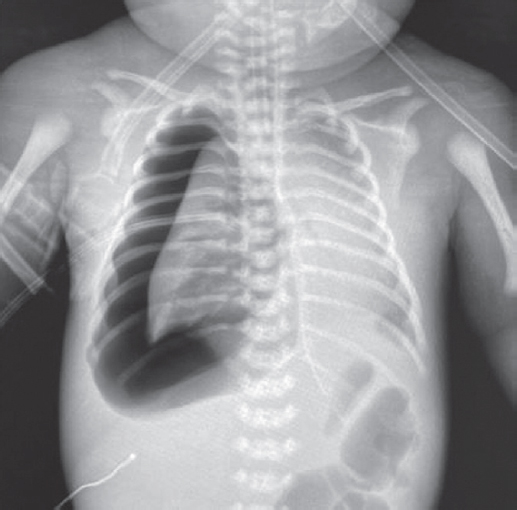

В статье представлен случай успешного лечения острого респираторного дистресс-синдрома у доношенного новорожденного, осложнившегося баротравмой легких, с применением монобронхиального введения экзогенного сурфактанта под рентгенологическим контролем. С целью оценки течения заболевания и эффективности лечения проведен ретроспективный анализ медицинской документации. С первых минут жизни у ребенка отмечались дыхательные расстройства, что стало основанием для проведения неинвазивной искусственной вентиляции легких. В динамике выявлено прогрессирование гиперкапнии и гипоксемии, в связи с чем была выполнена интубация трахеи и начата конвекциональная искусственная вентиляция легких с FiO2 = 1,0. Ключевой элемент терапии, позволивший достичь стабилизации состояния и регрессирования нарушений газообмена с полным выздоровлением пациента, — монобронхиальное введение экзогенного сурфактанта.

Монобронхиальное введение сурфактанта при остром респираторном дистресс-синдроме с гетерогенным поражением легких является эффективным вариантом лечения и может использоваться в клинической практике при рефрактерной гипоксемии.